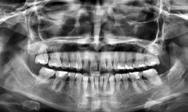

En la radiografía panorámica se observa 28 piezas dentales, con un diastema en los incisivos centrales (Figura 5).

En la radiografía panorámica (Figu ra 6) se observan 32 dientes, con los terceros molares en formación, adicionalmente la molar 46 con una